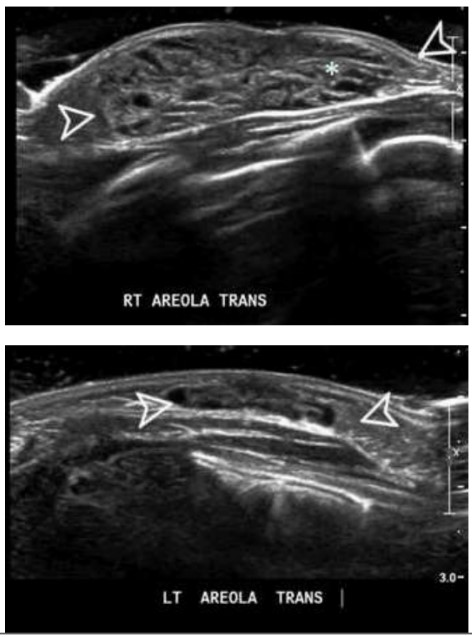

Recém-nascida (RN) do sexo feminino, com 10 dias de vida é levada ao consultório com aumento unilateral da mama direita, sem outras queixas (vide abaixo). A mãe nega comorbidades clinicas ou alterações durante a gestação e o parto.